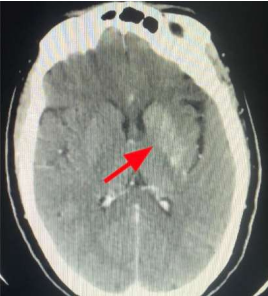

The cranial CT scan reveals a supratentorial intra-axial lesion adjacent to the left lateral ventricle body. It appears spontaneously hyperdense, rounded, well-defined, with heterogeneous enhancement after contrast administration. The lesion measures 11 x 9 mm and is associated with cortical veins draining into the deep collector vein. There is hyperdensity of the basal ganglia, more pronounced on the left, consistent with toxic/metabolic encephalopathy. Subsequently, a cranial MRI is performed, which indicates findings consistent with a left periventricular cavernoma. There are no signs of current complications, with an associated venous anomaly of development. Hyperintensity on T1-weighted images is observed at the head of the left caudate nucleus and lentiform nucleus, which do not enhance with gadolinium. These alterations in the left basal ganglia are compatible with non-ketotic hyperglycemic hemichorea.

Figure 1: Cranial CT scan showing hyperdensity of the left basal ganglia